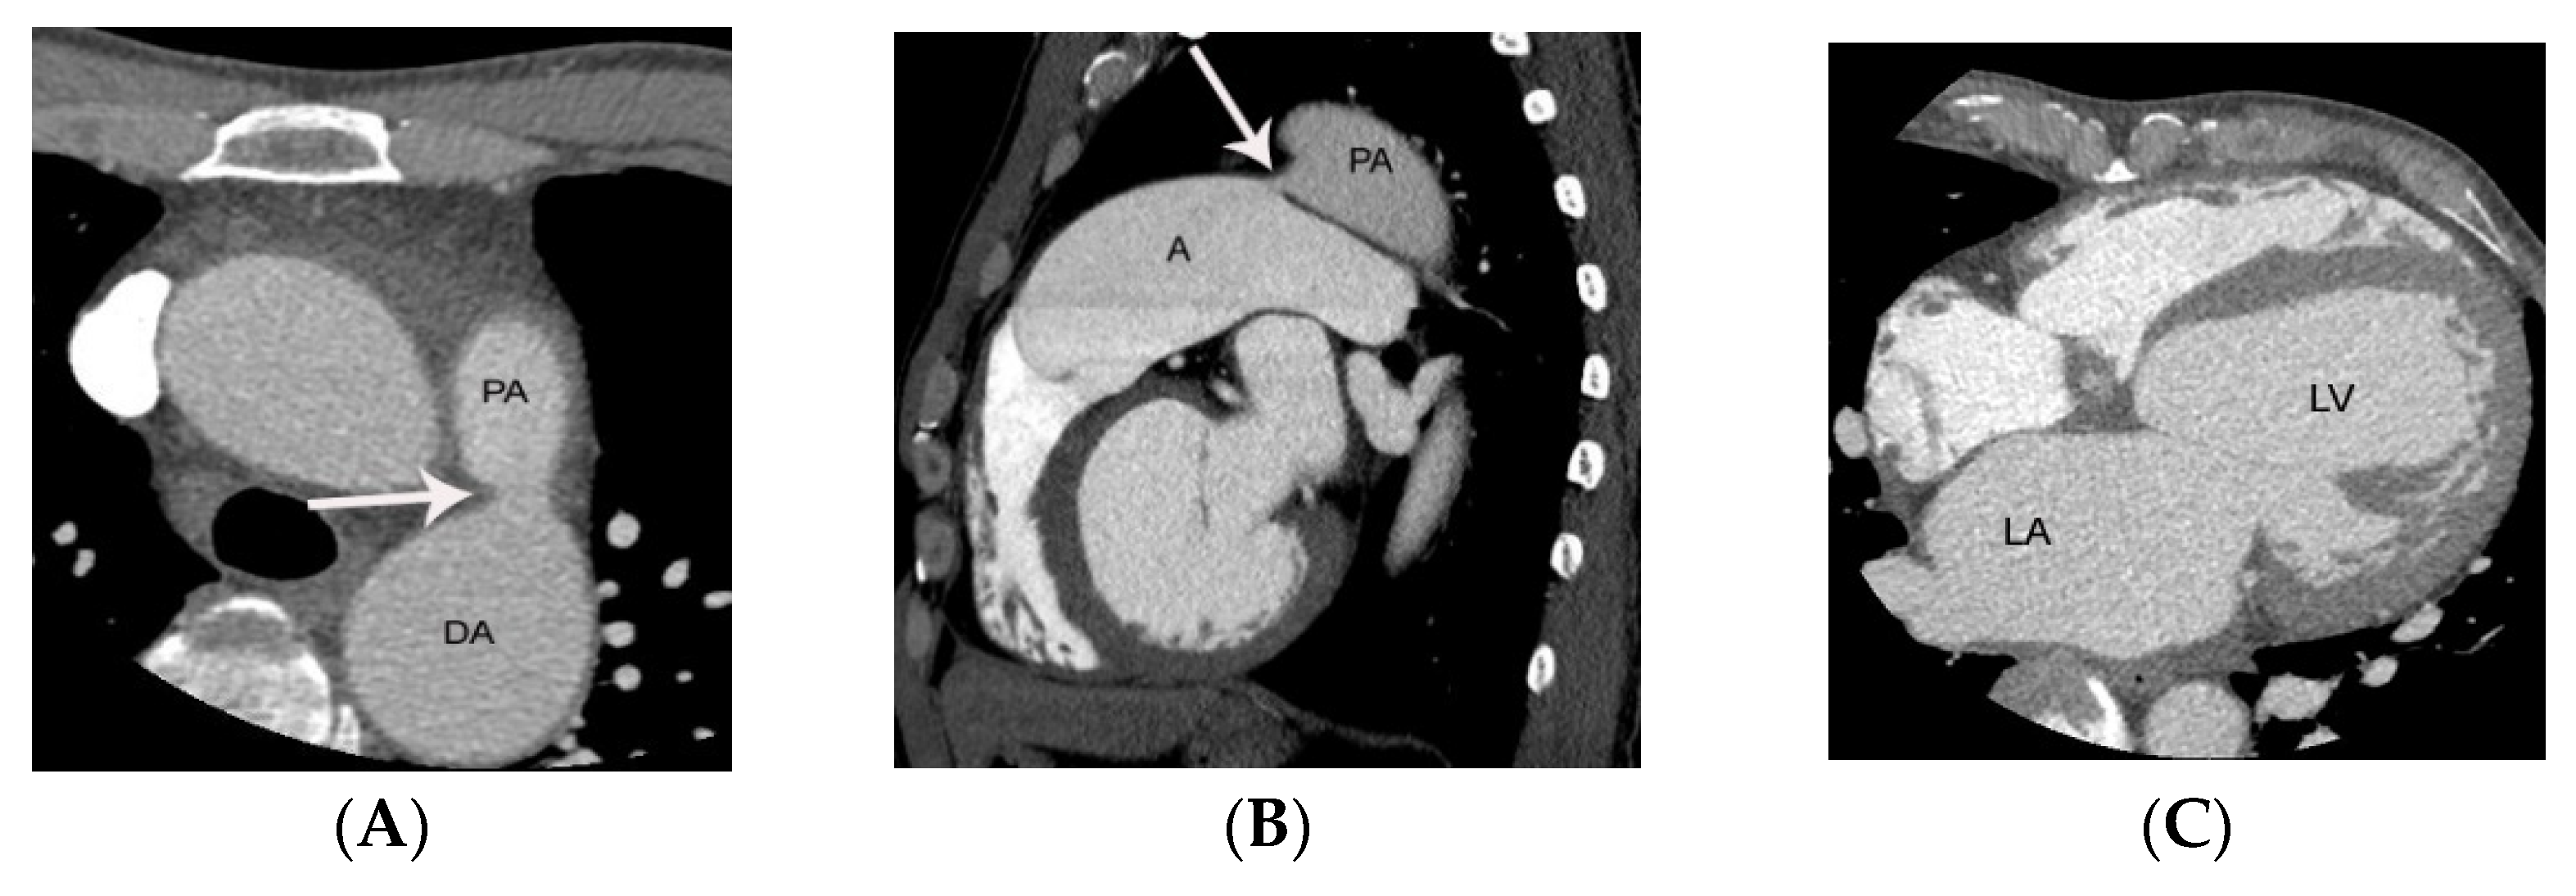

5. CT Anatomy of PDA